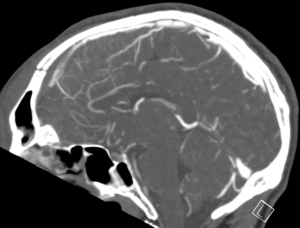

CASE 2 -A 54-year-old man walks into emergency 3 hours after a 150kg plank of wood fell on his head. He has obvious external signs of head injury and a cracking headache, however, neurologically he is intact. A CT head scan is performed

EXPLANATION –There is a depressed right parietal bone fracture with underlying pneumocephalus (indicates an open skull fracture) and a small subdural hematoma.

- Overlying this there is a scalp hematoma.

- There is also a non-displaced fracture in the frontal bone. This fracture crosses the midline and probably has injured the anterior aspect of the superior sagittal sinus.

- Tears of the dural venous sinuses may cause an extradural hematoma (EDH), as in this case. The hematoma is seen external to the compressed superior sagittal sinus.